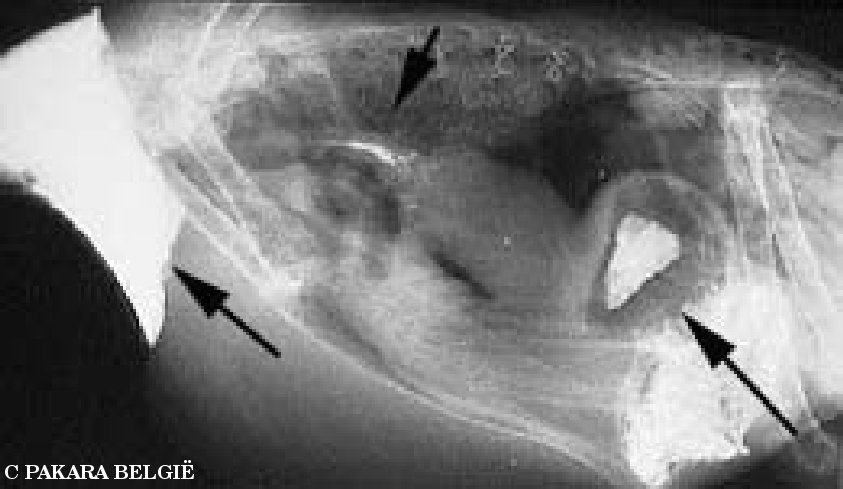

Hetgeen dat nu volgt is zo een röntgenonderzoek. Maar eerst nog een beetje

uitleg bij de foto's. De vogel ligt op zijn rechterkant met de kop naar links.

De eerste foto is van een normale vogel

De volgende foto toont duidelijk de enorm vergrootte kliermaag, aangegeven

door de pijltjes.

Op deze foto zie je de met barium gevulde krop uiterst rechts, er is barium in

de slokdarm (pijl in het midden). De spiermaag bezit ook barium (pijl uiterst

rechts), maar de vergrootte kliermaag heeft geen barium erin. De kliermaag kun

je zien juist links van de spiermaag.